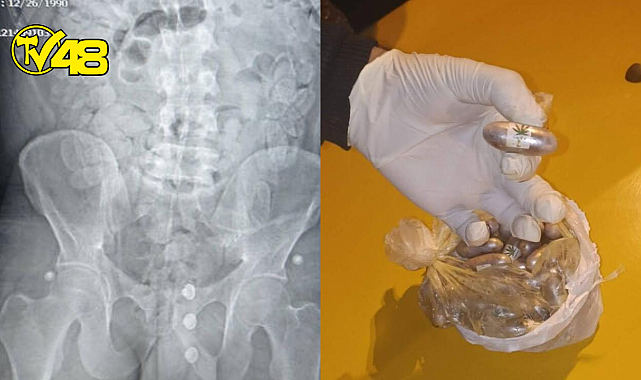

MİDE VE BAĞIRSAKLARINDA ÇOK SAYIDA KAPSÜL OLDUĞU TESPİT EDİLDİ

Yalova Cumhuriyet Başsavcılığı’nın talimatıyla Yalova Devlet Hastanesi’ne götürülen şüphelinin tomografisinde mide ve bağırsaklarında çok sayıda kapsül olduğu tespit edildi.

3 gün boyunca hastanede gözlem altına tutulan şüphelinin mide ve sindirim sisteminde bulunan 155 kapsül içerisinde bin 191 gram reçine esrarın da doğal yollardan çıkartması sağlandı.

Emniyetten yapılan açıklamada, ele geçirilen toplam 194 kapsül içerisinde bin 545 gram reçine esrarın, il genelinde bu zaman kadar piyasa değeri açısından ele geçirilen en yüksek miktarda uyuşturucu olduğu belirtildi.